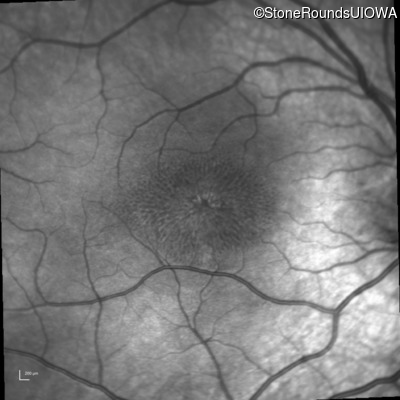

This 6 year old boy first experienced difficulty reading and seeing the blackboard at age 5.

Diagnosis & molecular findings

| XL Retinoschisis | RS1 | Pro192His CCC>CAC | XL |